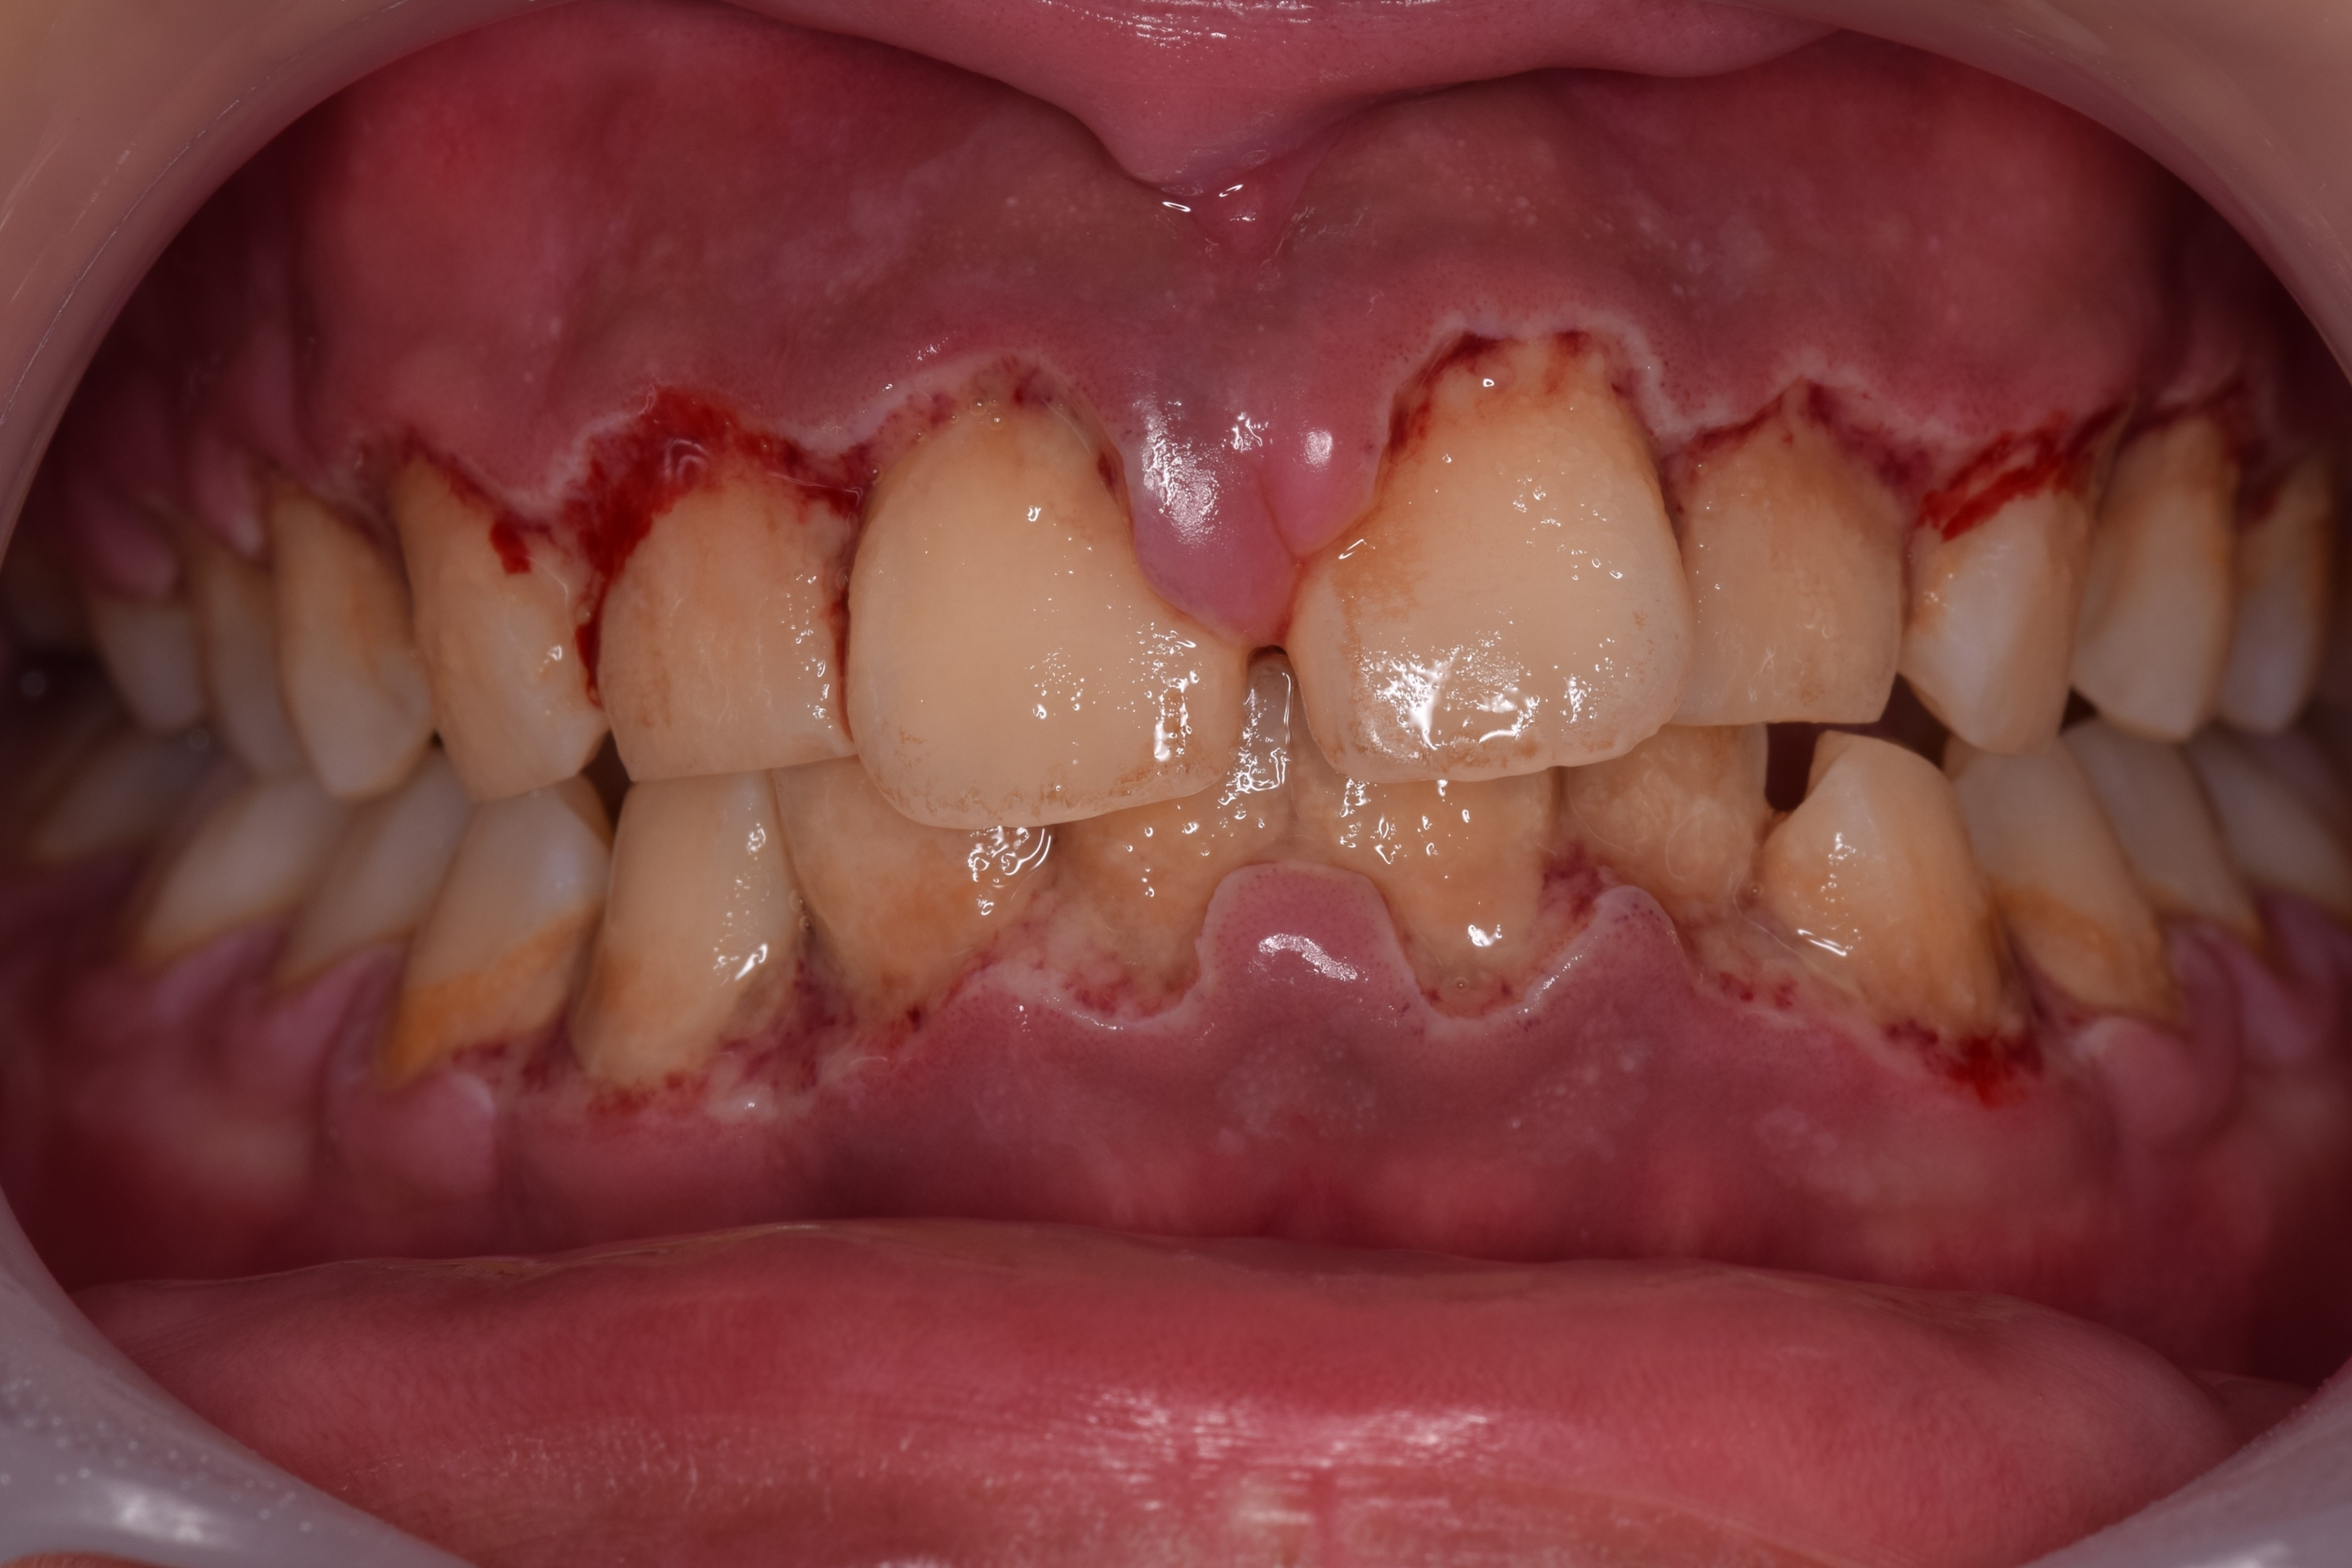

歯茎が腫れた原因は何ですか?

歯茎が腫れる一般的な原因は次のとおりです。

• 歯肉炎(歯肉の炎症)

• 感染症(ウイルスや真菌)

• 栄養失調

• 合わない入れ歯や歯科器具

• 妊娠

• 歯磨き粉やうがい薬に対する過敏症

• 歯と歯茎の間に食べ物のカスが詰まる

• 薬の副作用

歯肉の炎症や腫れの原因は他にも考えられます。

歯ぐきの腫れの根本原因を特定する最善の方法は、歯科医に症状を調べてもらい、正確かつ完全な診断をしてもらうことです。